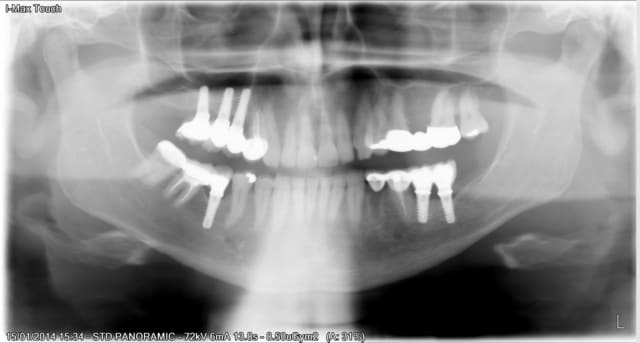

Patient qui vient pour faire un devis pour refaire son bridge en bas a gauche. La ceramique a explosée et dent 34 enlevée il y a un mois.

Son ancien prat lui a proposé de jumeler les implants avec la 35 et la 33 a tailler.Le patient judicieusement trouve le plan de traitement fumeux et vient pour un 2eme avis.

Ces implants ont été realisés en Espagne il a 2 ans.Aprés recherche sur oseosource je me demande s´il sagirait de Klockner.

J´avais vu juste le patient confirme "klockner nk2"

voilà ce que j'ai trouvé sur cet implant pas référencé sur osseosource...mais çà doit être le SK2...

Si ils sont sur osseosource mais sous le nom du fabricant soadco.